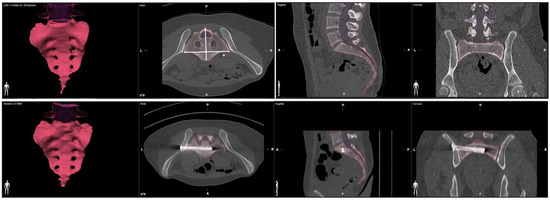

We processed an axial multi-planar bone kernel reconstruction (MPR) based on a preoperative and a postoperative computed tomography with a slice thickness of 1mm. We used the Brainlab Anatomical Mapping Software Package Version 1.1.1.8 of the Brainlab elements Software (Brainlab Inc., Munich, Germany) for volumetric measurement of the sacrum. The anatomical mapping software performs an automatic segmentation of the CT dataset and identifies the boundary of the sacral bone to process the volume of the sacrum. To ensure excellent data quality, we performed a manual post-processing of the automated reconstruction to adjust the exact borders of the sacral bone. We used the automatic volumetric report for calculation of the pre- and postoperative sacral volume (Figure 1). We measured the medio-lateral sacral diameter (MLSD) according to the Response Evaluation Criteria in Solid Tumors (RECIST) as the longest diameter of the sacrum within axial slices [15] (Figure 1).

Figure 1.

Volumetric measurement of the sacrum in preoperative and postoperative CT scans. Medio-lateral sacral diameter (MLSD) according to the Response Evaluation Criteria in Solid Tumors (RECIST) marked by *.